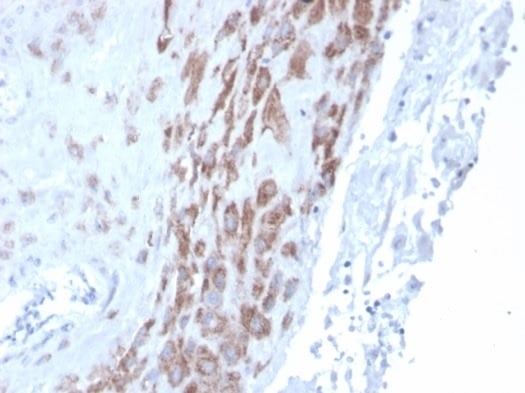

(Anti-GPR32 antibody IHC of human Ovary, Carcinoma. Immunohistochemistry of formalin-fixed, paraffin-embedded tissue after heat-induced antigen retrieval.)